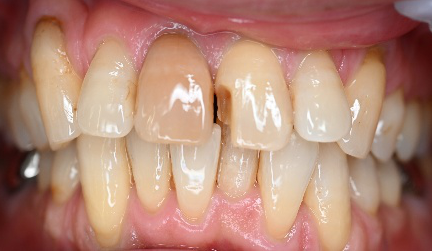

女性 Mさん 50代 (オールセラミック冠)

主訴

上の前歯をきれいにしたい。

治療内容

前歯3本にオールセラミック冠を被せて、歯並び及びすり減った歯を審美的に回復しました。歯ぎしりが強くあることがわかりましたので、マウスピースを使ってもらう事にしました。

所感

一番オススメな方法は、矯正をし、歯並びを整えた後、すり減って形が変わってしまった歯に被せ物をすることをお話ししました。患者さんは、3本に被せ物をすることにより歯並びをきれいにすることを希望されました。

治療後、「曲った前歯が長年コンプレックスでした。セラミックの歯の色合いや形が自然な仕上がりで、相談して本当に良かったです!神経を抜くこともなく治療ができ、予定よりも低料金にしてもらえたのがありがたかった。先生も、歯科衛生士さんも事務の人も皆、優しく寄り添った対応をしてくれました。ありがとうございました!」と、とても嬉しいお話しをしてくださいました。

オールセラミック冠3本:¥93,500(生活歯)×3本=¥280,500(税込)